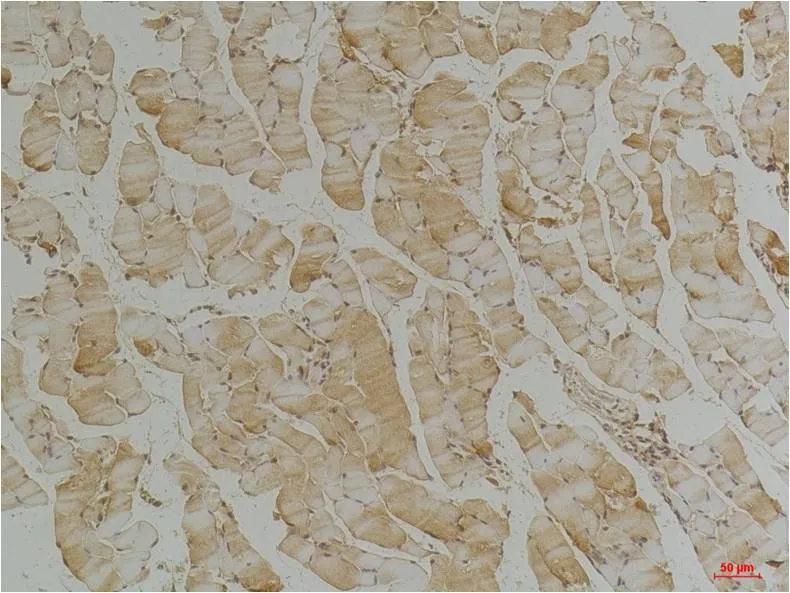

Desmin (4H1) Mouse Monoclonal Antibody

Cat: AMM00779